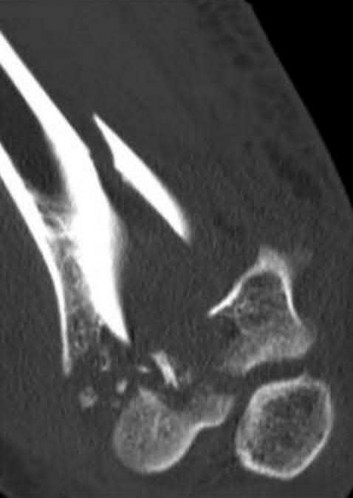

A 25-year-old female is involved in a motor vehicle collision. She presents with the isolated injury seen in Figures A through D. Her leg is swollen but her skin is intact. She has no clinical signs of compartment syndrome. Which of the following treatment options will allow for maintenance of fracture alignment and minimize the risk of soft tissue complications?

1) Closed reduction and long-leg non-weight bearing cast

2) Immediate open reduction of the tibia through an anterolateral approach

3) Percutaneous fixation of the articular surface and intramedullary nailing

4) Definitive uniplanar external fixator

5) Immediate open reduction of the tibia through an anteromedial approach

The patient presents with a closed distal third metaphyseal-diaphyseal distal tibia fracture with simple intra-articular extension. Immediate intramedullary nailing along with percutaneous fixation of the articular component provides appropriate restoration of length, rotation and alignment and minimizes the risk of wound complication.

Displaced distal third tibia fractures may be associated with simple intraarticular extension. Operative treatment of intra-articular distal tibia fractures has historically been performed with open reduction and internal fixation. Early open reduction and plate fixation of pilon fractures has been associated with high rates of infection and wound complication. In select patterns with simple articular extension, percutaneous screw fixation and medullary nailing may provide appropriate reduction with minimal soft-tissue risk.

Marcus et al. evaluated the outcomes of immediate intramedullary nailing and percutaneous fixation of simple intra-articular distal tibia fractures (AO/OTA 43 C1 and C2). The authors found excellent rates of union and alignment, however caution against broad application of this technique until more rigorous randomized studies can be performed.

Sirkin et al. retrospectively evaluated the results of a staged approach to management of intra-articular distal tibia fractures with temporary bridging external fixation followed by open reduction and internal fixation (ORIF). The authors found decreased rates of wound complication and infection compared with prior studies.

Figures A and B demonstrate a distal third tibial shaft fracture with simple intra-articular extension. The axial and coronal CT cuts in Figures C and D further clarify the articular injury. Illustrations A and B demonstrate a comminuted distal third tibial fracture with simple intra-articular extension. Illustrations C and D are fluoroscopic images of the same injury after intramedullary nailing and percutaneous fixation of the articular component.